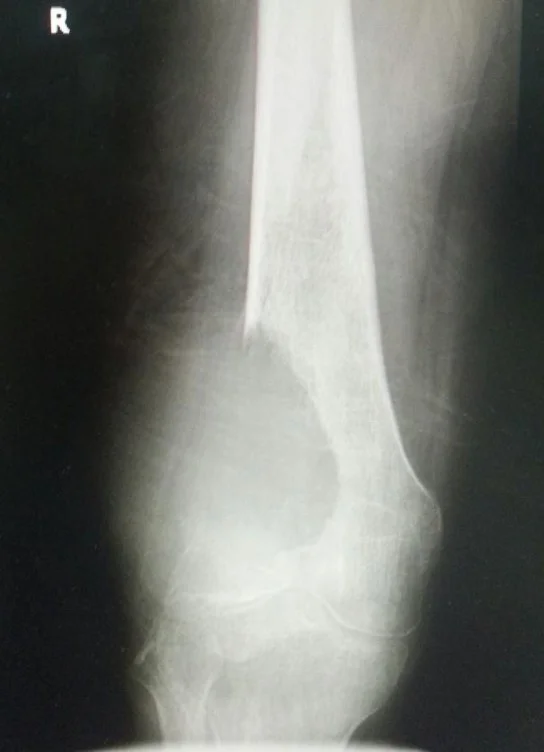

Trauma